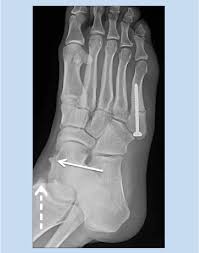

Stress fractures of the medial malleolus in the professional soccer player demonstrate excellent outcomes when treated with open reduction internal fixation and arthroscopic spur debridement anthony nguyenian beasleyjames calder knee surgery, sports traumatology, arthroscopy. Case contributed by dr henry knipe ◉ ◈. Medial malleolus and talus make up the medial side. The medial malleolus is the prominence on the inner side of the ankle, formed by the lower end of the tibia. What is the largest tendon of the calcaneus?

Traumatic dislocation of tibialis posterior presenting late as a bony spur. The relationship between spur formation, the medial tubercle of the calcaneus and intrinsic heel musculature results in a constant pulling effect on the plantar fascia resulting in an inflammatory. It may also involve injury to a ligament. What are treatment options for a bone spur? The medial malleolus is the largest of the three bone segments that form your ankle. Small well corticated bony fragments lies at the anterior aspect of the medial malleolus. The other two are the lateral and the posterior malleolus. The medial malleolus is the medial projection of bone from the distal tibia. Bone spurs are bony projections that develop along bone edges. The tibia (shin bone) is the medial bone of the leg and is larger than the fibula, with which it is paired (figure 3). The fibula is commonly shortened and externally rotated in a malunion, although only one of these may be present, determining the type of osteotomy and bone. Ankle joint dislocation is often associated with fracture of medial malleolus bone. Nkle sprain, medial malleolus, pseudoarthrosis radiographs of the medial malleolus showed jagged.

Figure 2 From Medial Impingement Of The Ankle In Athletes Semantic Scholar

Figure 2 From Medial Impingement Of The Ankle In Athletes Semantic Scholar from d3i71xaburhd42.cloudfront.net